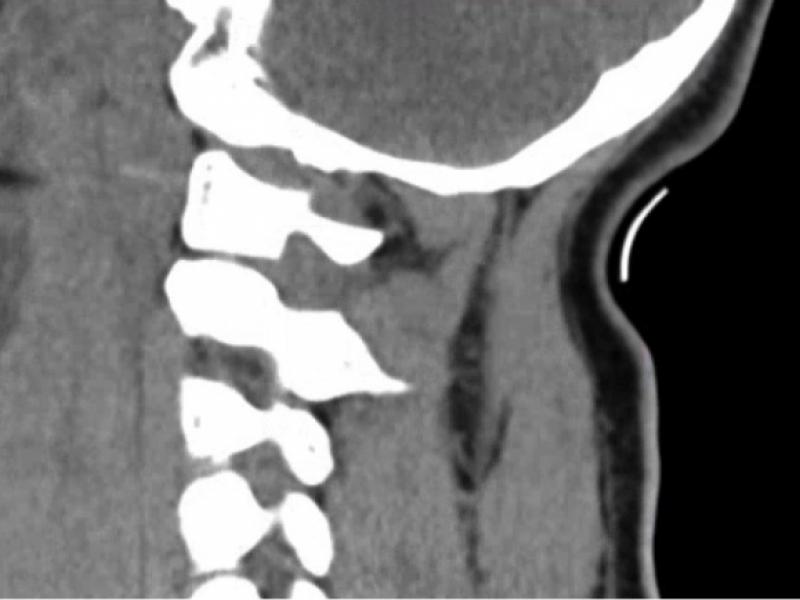

A 29 yo male presents from a high speed MCV. He was the